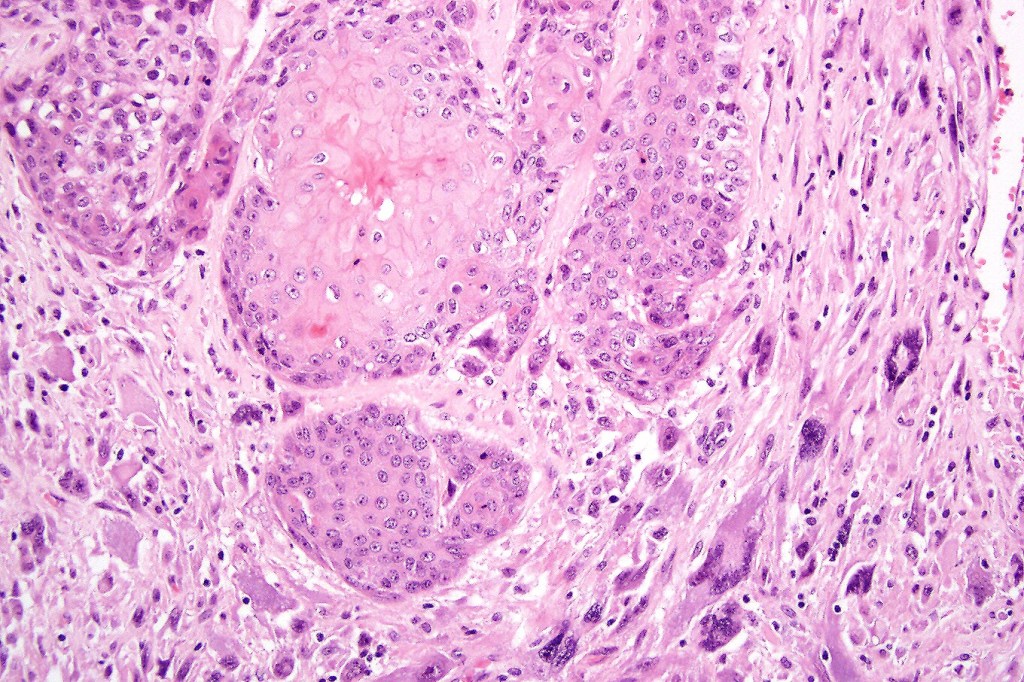

•Biphasic tumor

•Admixture of squamous carcinoma & pleomorphic spindled cell, osteoid, chondroid, MFH-like +/- osteoclast-like giant cells & rarely, smooth muscle, skeletal muscle, myofibroblastic or angiosarcomatous elements